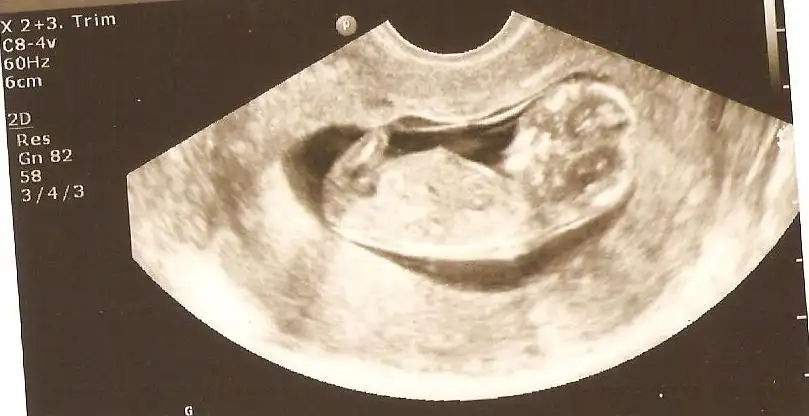

Ben meraktan gercekten catlicam sanirim :)

21. Hafta ve hala ogrenemedim. Son randevuda doktor daha kucuk bir dahakine bakacagim dedi :KK43:

Tahminde bulunursaniz gercekten cookk sevinirim

Coktandir giremiyorum arkadaslar.yarin ikili testim var.cok ama cok meraktayim .tekrar ekliyorum 10 haftalik ultrason goruntusunu.bi bakiverin nolur.dua alirsiniz